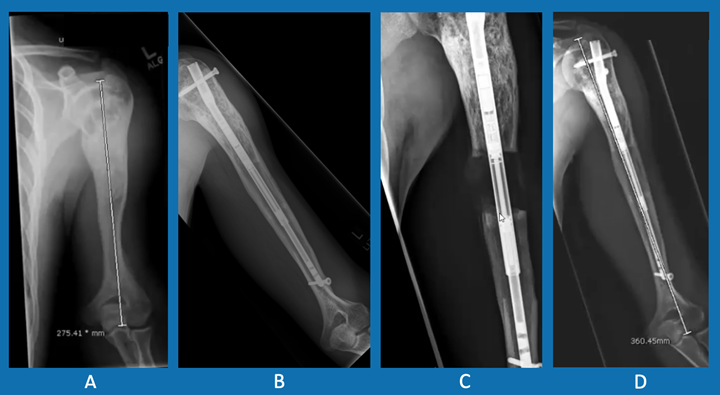

Left humerous lengthening process

Left humerus: A. prior to lengthening; B. one year after initial lengthening of ~4.5 cm using a PRECICE nail; C. immediately after second lengthening of ~4.5 cm; D. six months after second lengthening.